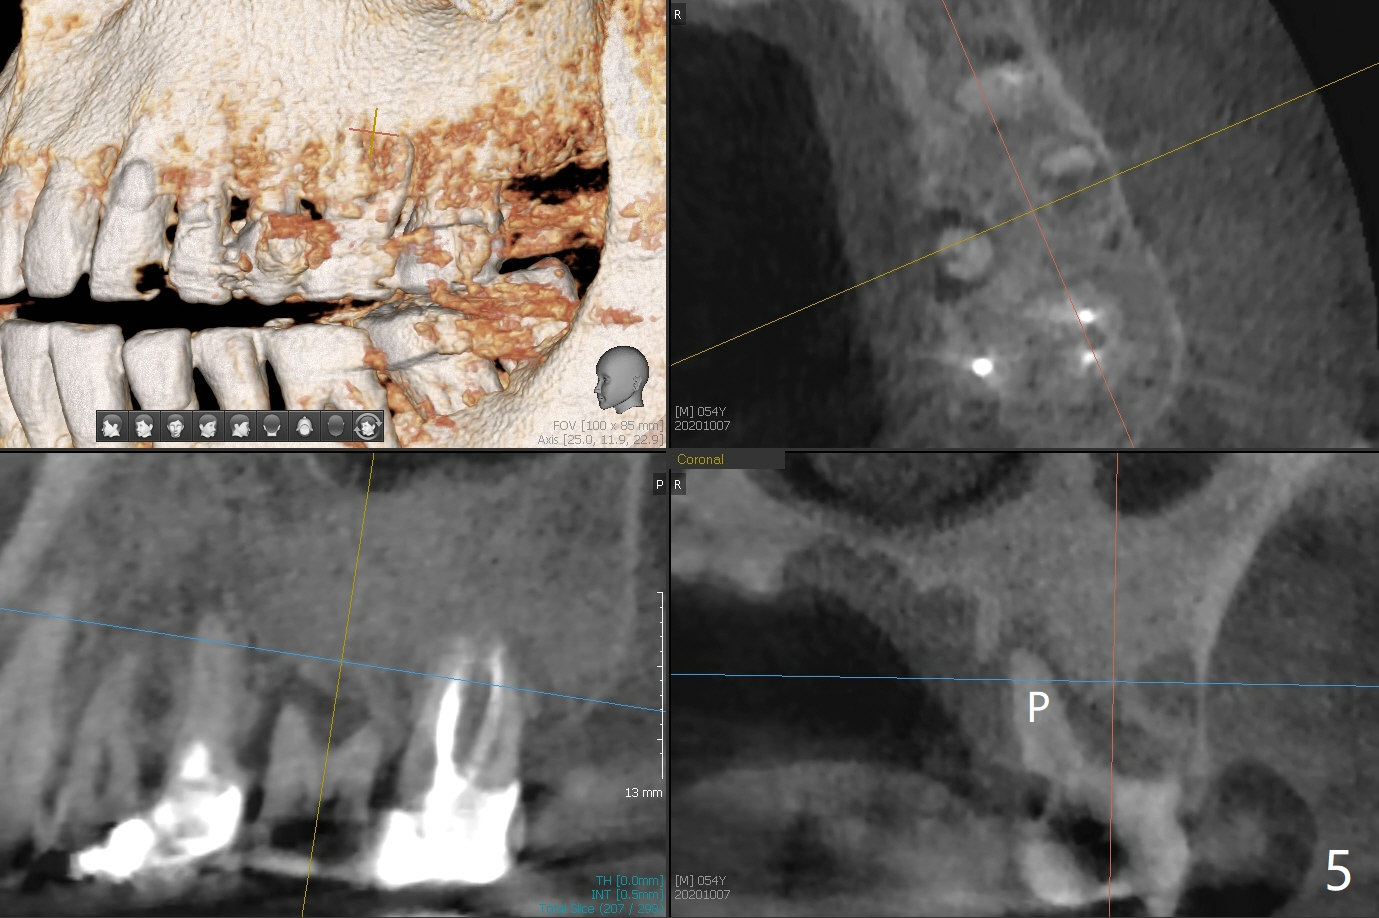

54岁男牙齿问题好像与牙周病和咀嚼力大有关(图一),虽然右上3(图二)和左下6(图三,四)需要治疗,因为疼痛他要求先处理左上6(图五)。后者腭侧根骨质吸收严重,植体尽量颊侧植入(图六),4.5 或者5.0x11毫米。放置粘性骨粉至植体平台,为了简化术中基台放置,使用Non-Hex Temporary Abutment,临时牙冠做的尽量大,占据牙槽窝空间,最后将PRF膜塞入两者之间。Return to Prevent Molar Periimplantitis (Protocols, Table) No Deviation No Caries Metronidazole CT/前牙植牙 Socket Shield Xin Wei, DDS, PhD, MS 1st edition 10/11/2020, last revision 02/21/2021